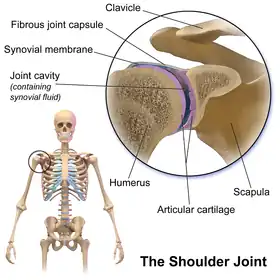

The shoulder joint (or glenohumeral joint from Greek glene, eyeball, + -oid, 'form of', + Latin humerus, shoulder) is structurally classified as a synovial ball-and-socket joint and functionally as a diarthrosis and multiaxial joint. It involves an articulation between the glenoid fossa of the scapula (shoulder blade) and the head of the humerus (upper arm bone). Due to the very loose joint capsule that gives a limited interface of the humerus and scapula, it is the most mobile joint of the human body.

Structure

The shoulder joint is a ball-and-socket joint between the scapula and the humerus. The socket of the glenoid fossa of the scapula is itself quite shallow, but it is made deeper by the addition of the glenoid labrum. The glenoid labrum is a ring of cartilaginous fibre attached to the circumference of the cavity. This ring is continuous with the tendon of the biceps brachii above.

Capsule

The shoulder joint has a very loose joint capsule, which can sometimes predispose the shoulder to dislocate.

Bursae

A number of small fluid-filled sacs known as synovial bursae are located around the capsule to aid mobility:

- Between the joint capsule and the deltoid muscle is the subacromial-subdeltoid bursa.

- Between the capsule and the acromion is the subacromial bursa.

- The subcoracoid bursa is between the capsule and the coracoid process of the scapula.

- The coracobrachial bursa is between the subscapularis muscle and the tendon of the coracobrachialis muscle.

- Between the capsule and the tendon of the subscapularis muscle is the subscapular bursa, this is also known as the subtendinous bursa of the scapularis.

The supra-acromial bursa does not normally communicate with the shoulder joint.